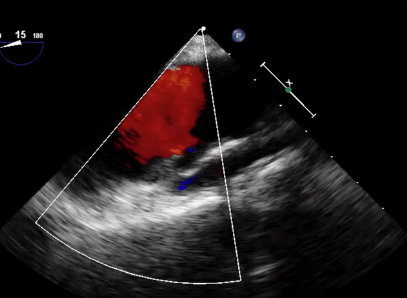

Transesophageal echocardiogram (Videos 1-6) demonstrated a mobile echodense mass suggestive of a thrombus on the surface of ascending aorta, in a patient with atrial fibrillation. The aortic root and ascending aorta were normal in size and nonaneurysmal in this case.